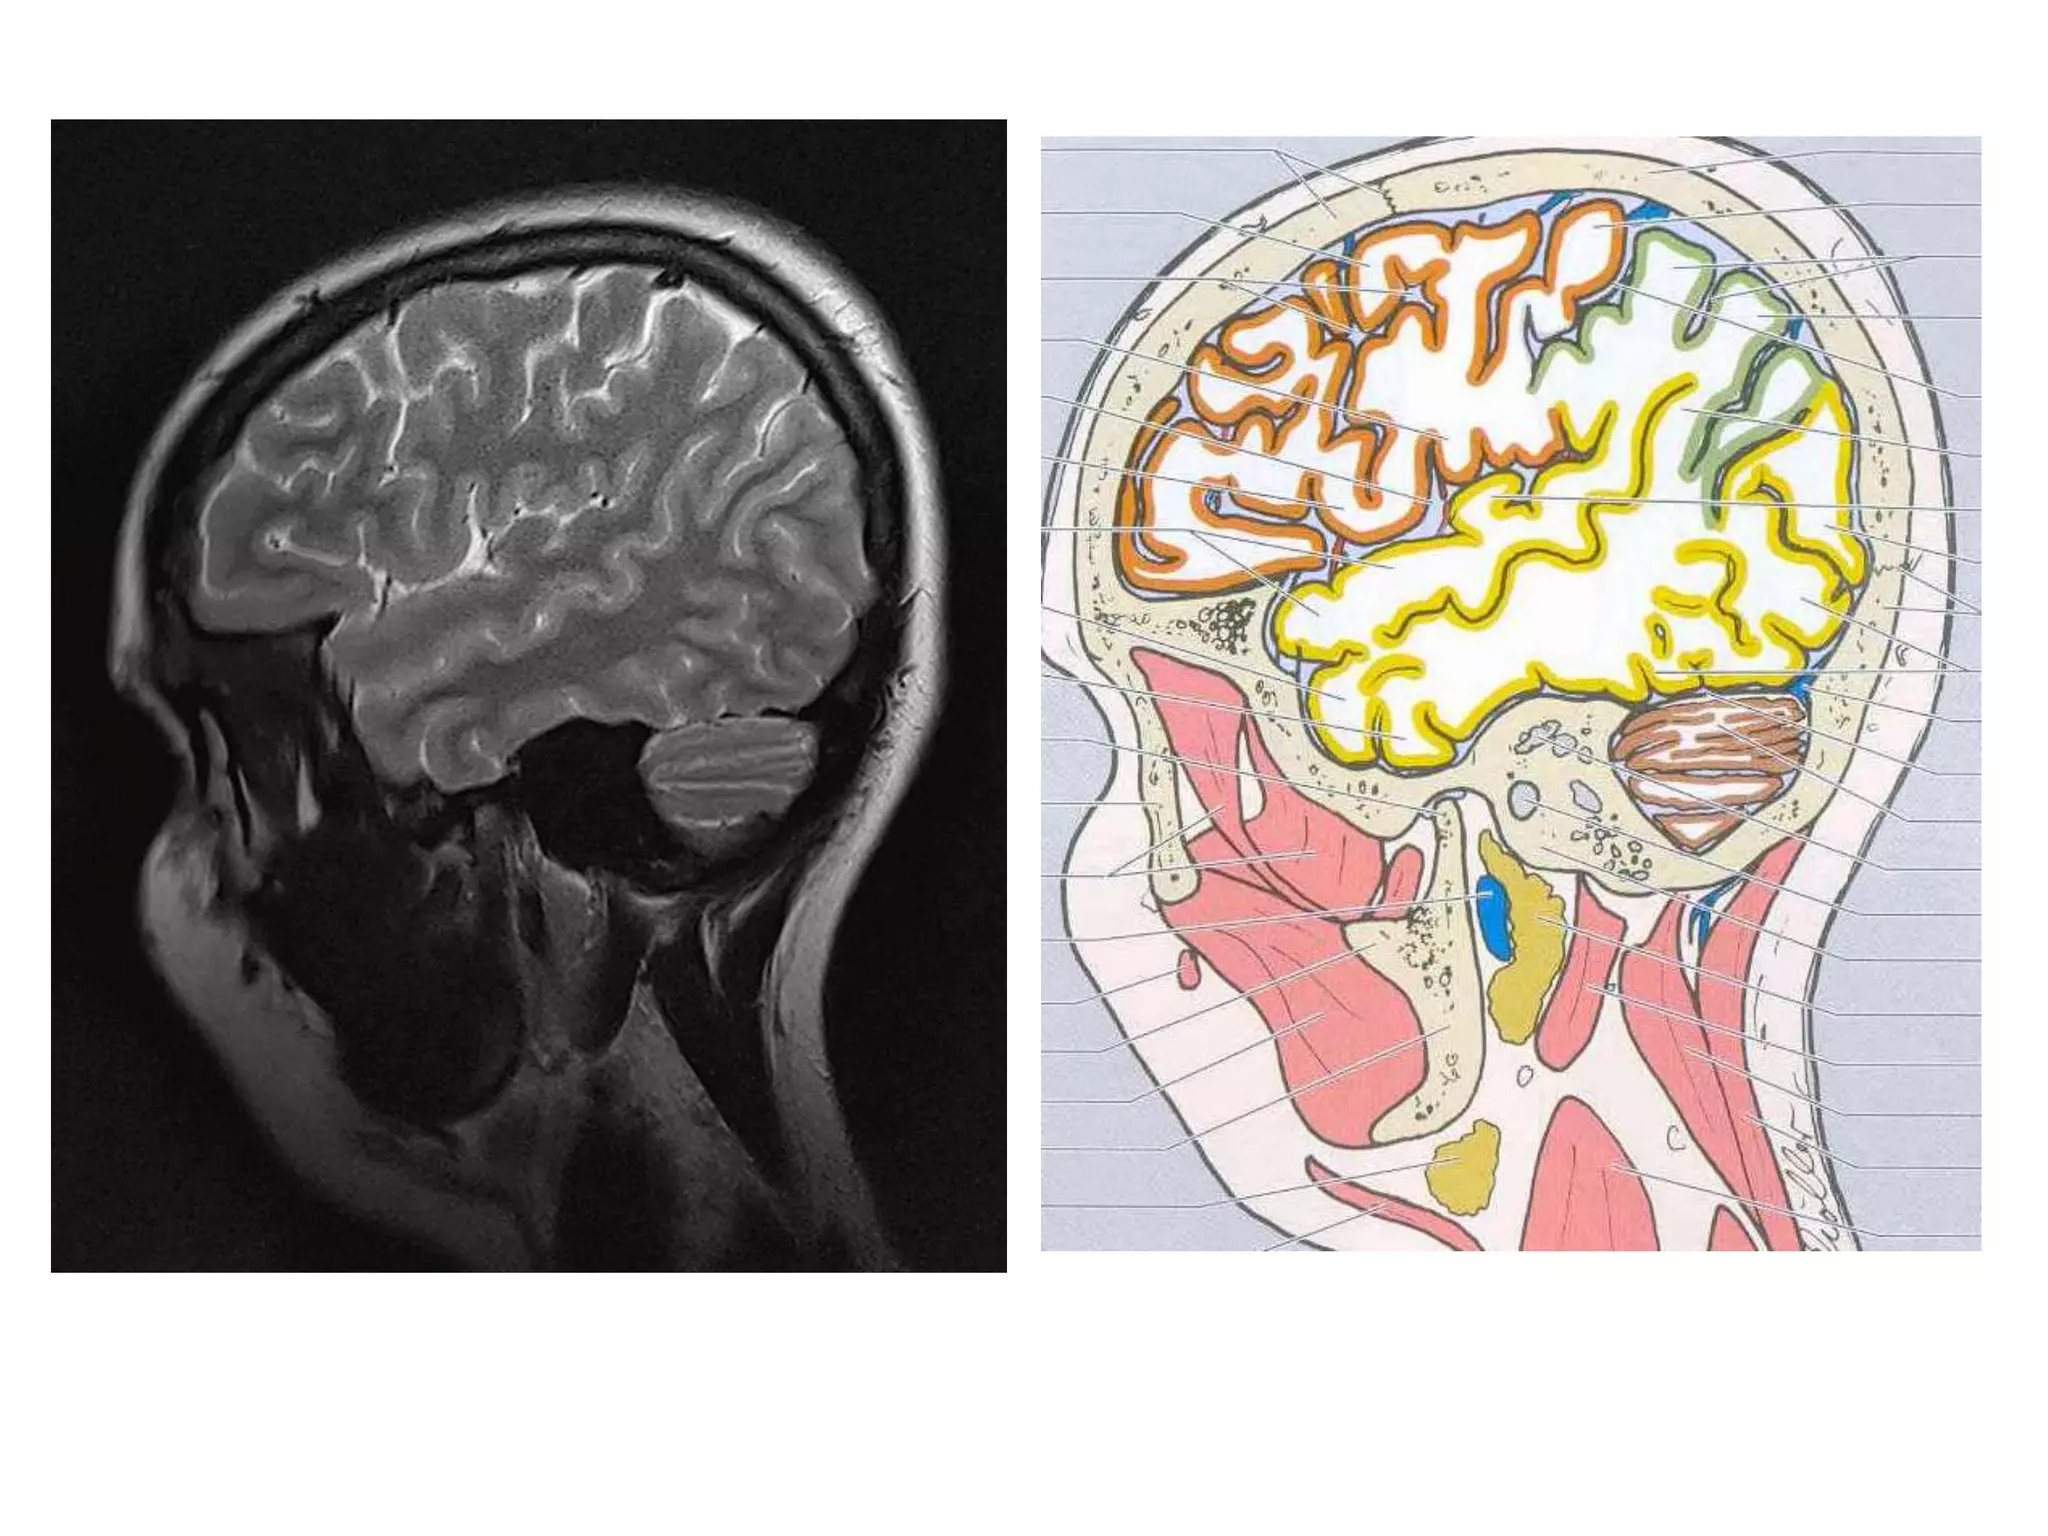

• Anatomy of cerebral hemispheres and mid brain – T1 W

MRI.

• Internal grey - white matter areas – T2 W MRI.

• In Cerebral hemispheres , white matter above the level of

lateral ventricles is called centrum semiovale

• Saggital and Coronal T1 weighted MRI – accurate

assessment of ventricles and C. callosum